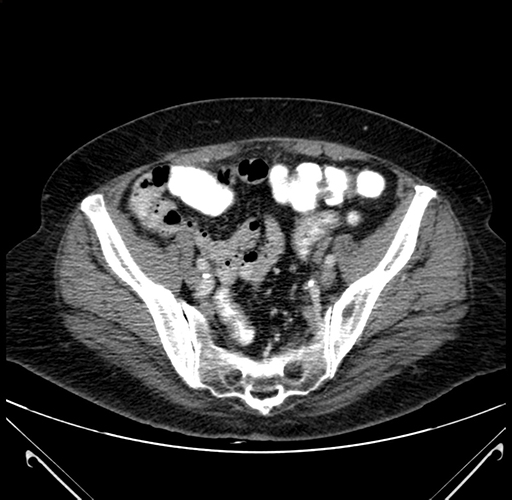

Pre-Chemo: Axial Venous

Axial Venous